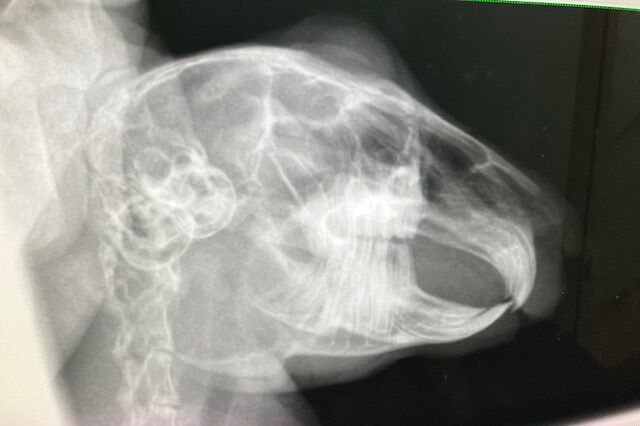

術前検査のレントゲン

特に問題ありません。

※クリックで拡大見れます。

切歯もキレイ